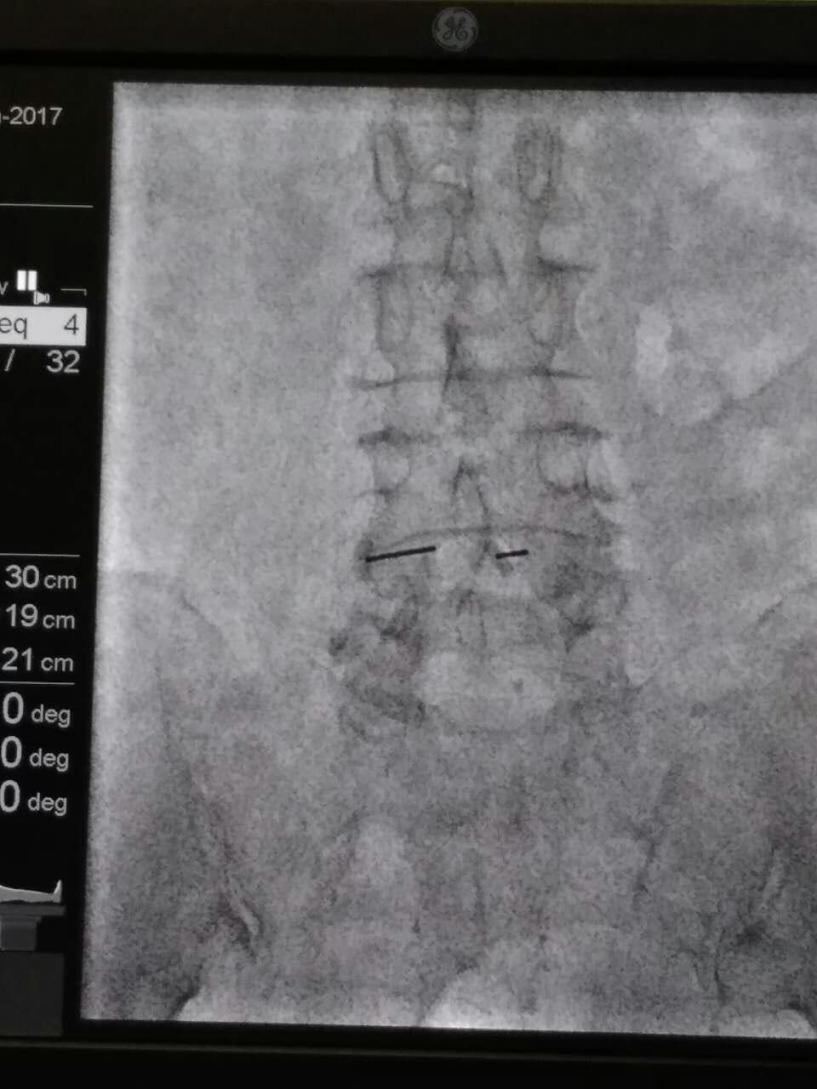

术中,为了定位透照期间为了防避免老人害怕和随时监测,我们团队的杨大夫穿上铅衣陪同老人。由于准备充分,配合给力,手术也异常顺利,半个小时结束。术后的当天中午患者就能和家属坐起来一起吃饭了,家属说这是几个月来的第一次。第二天老人就推着轮椅可以走个不停。前些天我们随访,患者的儿子说:“老人现在每天都下楼两趟溜溜弯。以前,担心老人下不了床;现在,我们担心老人走丢了。”